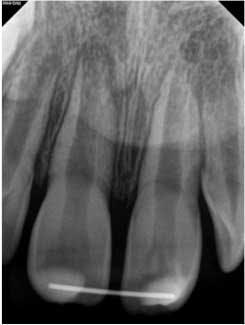

At three months, the clinical testing was equivalent and radiographs showed a fracture still present, but the periodontal ligament (PDL) and lamina dura (LD) were intact and uniform, especially near the fracture line (figure 2). At six months, there was no change in the response to vitality testing and radiographs continued to show no deleterious changes (figure 3).